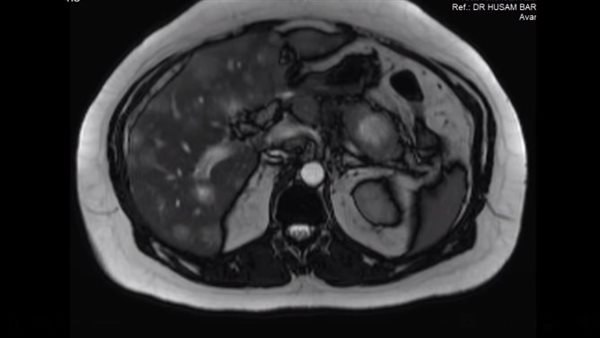

وبعد مزيد من الفحص تبين أن الرجل يعاني حالة مرضية نادرة، وزاد إفراز هرمون الحمل بسبب ورم في البنكرياس منتشر إلى الكبد، وحصل الفريق الطبي على عينات من ورم الكبد وفحصها تحت المجهر وتحت الأشعة المقطعية.

وذكر الطبيب الأردني، أن فحص الحمل كان إيجابيا نتيجة إفراز هرمون الحمل من ورم في البنكرياس منتشر للكبد، موضحا أنه بعدما أخذ عينات من ورم الكبد تحت الأشعة المقطعية وفحصه تحت المجهر تبين أن الورم يفرز هرمون الحمل.